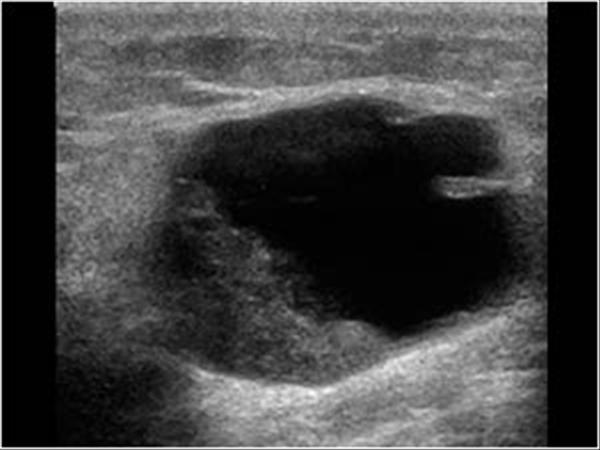

Ung thư vú - Ảnh 3

Ung thư vú

» Thông tin: Nữ giới – 82 tuổi.

» Lâm sàng: Khối tuyến vú.